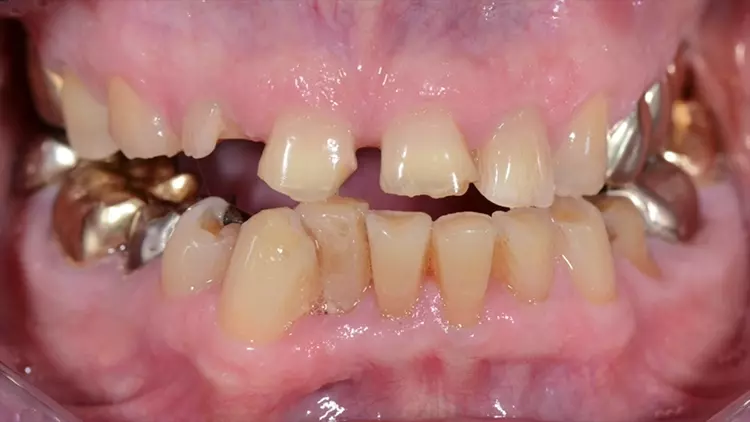

Ihr Videofilm dokumentiert die Rehabilitation des frakturierten Frontzahns 12 sowie der verloren gegangenen Vertikaldimension aufgrund erosiven Zahnhartsubstanz-Verlustes bei einem 75-jährigen Patienten. Die Behandlung wurde in 3 Bisshebungsphasen gegliedert. Gezeigt wurde die digitale Herstellung einer Polycarbonatschiene sowie eines non-prep Langzeitprovisoriums aus Hybridkeramik.Während der Tragephase der Schiene können sowohl Daten für die finale Versorgung gesammelt sowie Änderungen hinsichtlich Phonetik, Ästhetik oder Funktion vorgenommen werden. Durch die Hinterlegung der Datensätze sind auch Modifikationen bei der Gestaltung des LZP sowie der späteren keramischen Versorgung jederzeit möglich.

Aini, Awiszus, Bornmann